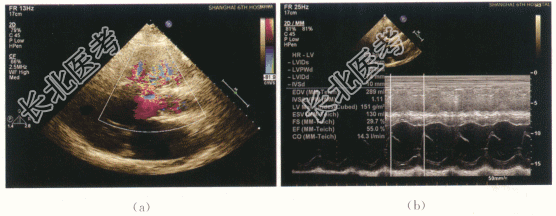

- [材料题] 患者,男性,24岁。出生后体检发现心脏杂音,诊断为"先天性心脏病",具体不详。无发绀无蹲踞,日常活动不受限制,生长发育正常。5年前开始出现活动后心悸,无明显胸闷气急,无黑矇头晕,未治疗。1年前无明显诱因出现心前区疼痛,自诉为刀绞样痛,持续1~2min,伴心悸、出冷汗,无发热,无头晕黑矇,与是否活动及体位无关,服药后缓解,具体用药不详。患者既往否认高血压病史。否认糖尿病病史。有心脏病病史24年。否认慢性肾脏疾病史。体格检查:患者心脏相对浊音界有明显扩大。心率80次/min,节律齐,正常第一心音,P2亢进。胸骨左缘3、4肋间可闻及吹风样收缩期杂音向颈部传导。实验室检查及特殊检查:RBC、Hb升高、ESR增高。心电图:窦性心律,左心室高电压。影像资料如下: